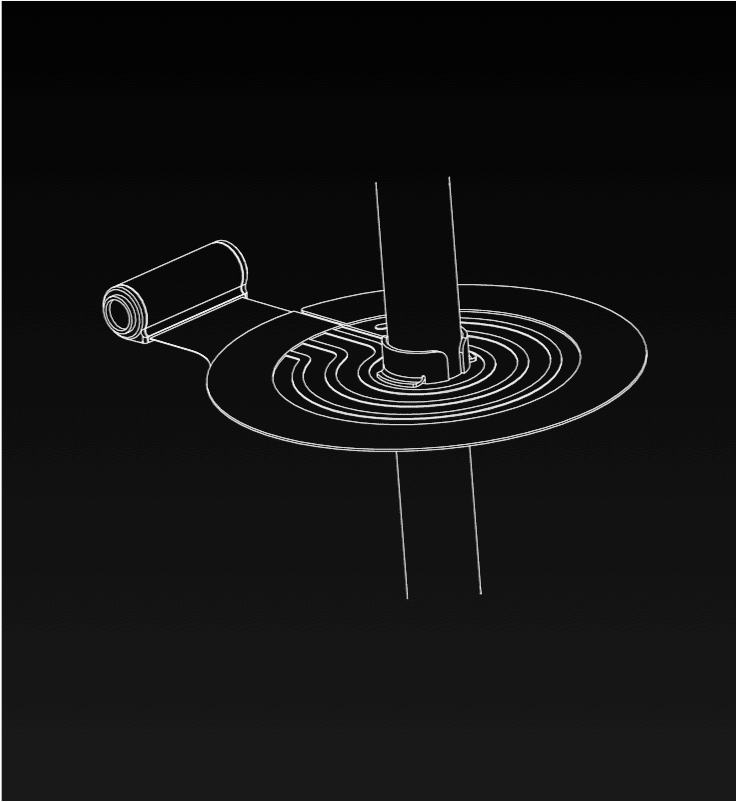

Dual Lumen Cannula

16 Novel Claims

The proprietary Convertible Dual Lumen Cannula is uniquely designed to offer multiple uses with intravascularly converting from a single-lumen cannula into a dual-lumen cannula after initial insertion. The unique cannula may potentially allow for fast action and reduced risk, complications and additional infection points.

An essential tool in a wide range of medical settings

A dual-lumen cannula is often used for the simultaneous venous drainage and reinfusion of blood during processes such Extra-Corporeal Membrane Oxygenation (ECMO) in Intensive Care Units (ICUs).

An essential tool in a wide range of medical settings

A dual-lumen cannula is often used for the simultaneous venous drainage and reinfusion of blood during processes such Extra-Corporeal Membrane Oxygenation (ECMO) in Intensive Care Units (ICUs).

Dual lumen cannula

- Granted in the U.S., 2023*

- Granted in the U.S., 2023

- Filed in Europe, China, Korea, Japan, Israel

A cannula fixation device

- Granted in the U.S. 2024

- Granted in Israel, 2022